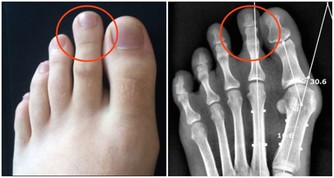

6、腳部腫脹;

7、骨痛。